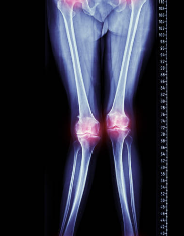

비타민 D 결핍은 골다공증, 골연화증, 골절 등 뼈 건강에 문제를 일으키는 질환과 관련이 있습니다. 그리고 비타민 D 결핍으로 인해 발생하는 골병 중에 하나가 구루병입니다.

구루병은 뼈의 염증과 골감소, 그리고 골 조직이 변성되는 질환으로, 비타민 D 결핍이 가장 일반적인 원인 중 하나입니다. 구루병은 일반적으로 노인에서 발생하는데, 나이가 들면 피부에서 비타민 D가 합성되는 능력이 저하되기 때문입니다. 또한, 비타민 D를 충분히 섭취하지 못하는 식습관이나 지역적인 문제 등도 구루병 발생 위험을 높일 수 있습니다.

구루병은 주로 다리 뼈나 골반 부위에서 발생하는 통증과 함께 보행 불편, 근육 약화, 골절 등의 증상을 유발합니다. 구루병은 비타민 D 결핍을 예방하고 치료함으로써 예방할 수 있습니다.